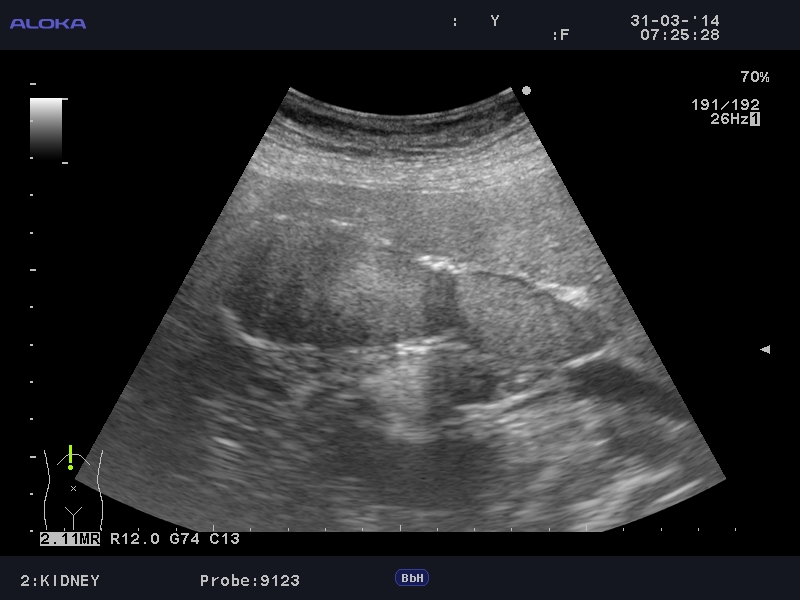

Еще случай.

Бабушка из отделения сестринского ухода, без жалоб на боли в животе. Лаб. анализы не изменены.

Дифдиагноз

Острый эмфизематозный холецистит.

Клиника + реверберация а не тень + подвижность газа.

Если кальциноз стенки полный и содержимое пузыря осмотру не доступно, то есть показания к проведению КТ-МРТ. Если стенки инкрустированы частично (как в представленных случаях) и можно оценить характер содержимого и структуру стенок, то можно ограничиться только УЗИ. Далее, если есть подозрение на опухоль то пациента направляют к онкологу, а он сам определяет дальнейшую тактику.